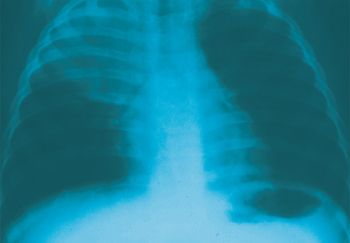

Respiratory symptoms are a major reason why outpatients seek medical care, and primary care physicians who treat children frequently see pneumonia. This week’s photo essay tests your knowledge of respiratory problems in kids.